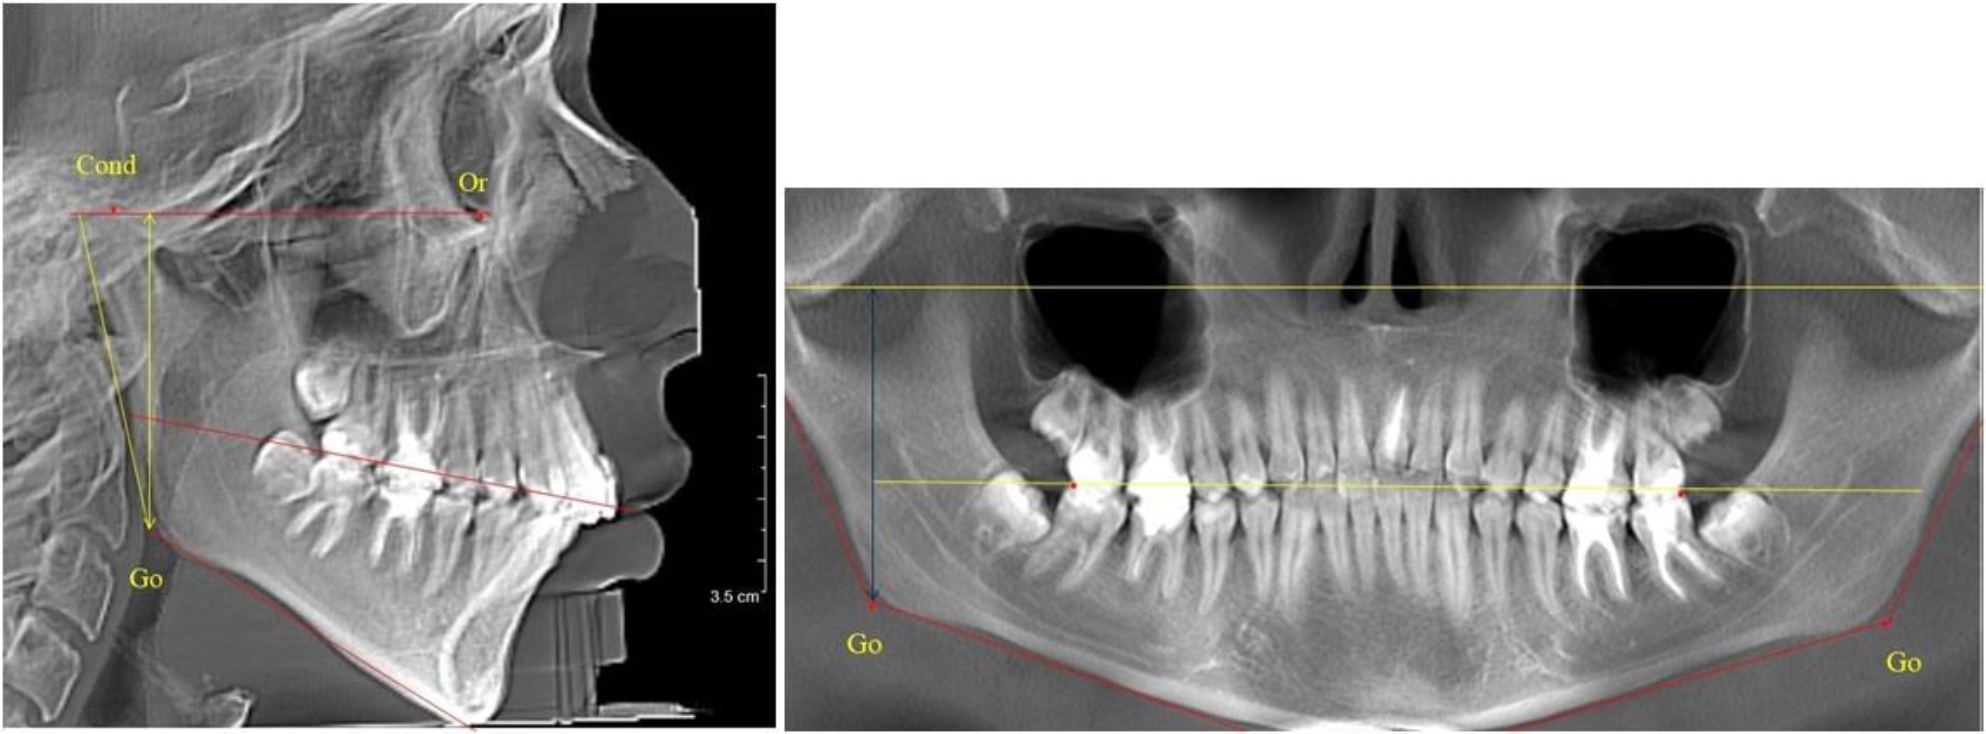

В 1-й группе были проанализированы 7 телерентгенограмм и 7 ортопантомограмм, что составило (6,60 ± 2,41) % от числа изученных рентгенограмм. На всех парах рентгенограмм угол нижней челюсти, измеренный на телерентгенограмме, соответствовал углу, полученному при построении угла на ортопантомограмме. Окклюзионная линия практически однотипно делила ветвь на два отдела (рис. 1).

Как на ортопантомограмме, так и на телерентгенограмме высота ветви у детей в периоде сформированного прикуса молочных зубов составляла (42,21 ± 2,48) мм. При этом высота верхней окклюзионно-суставной части была (22,57 ± 1,46) мм, а нижней – (19,64 ± 1,54) мм.

Учитывая вариабельность абсолютных величин, определи относительные показатели соразмерности частей ветви нижней челюсти. Так, отношение высоты верхней части ветви к нижней в среднем составляло 1,15 ± 0,13. Отношение общей высоты ветви к верхней ее части составляло 1,87 ± 0,14, а отношение общей высоты ветви к нижней ее части было 2,14 ± 0,16 и достоверных различий по относительному показателю отношения всей высоты к верхней и нижней челюсти нами не отмечено (р ˃ 0,05). При этом визуально обе части выглядели примерно равноразмерными.

Рис. 1. ТРГ и ОПТГ пациента 1-й группы

Рис. 2. ТРГ и ОПТГ пациента после прорезывания первых постоянных моляров